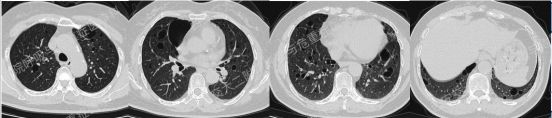

患者呼吸道症状并无太多特异性,还是从影像资料入手,右肺中叶外侧段高密度灶并纵隔及右肺门淋巴结肿大,同时存在双肺多发囊性病变,一元论?多元论?

患者实验室常规检查项目无明显异常,结核感染T淋巴细胞:测定管-阴性对照管1685.11pg/mL,阳性(+)PPD试验++;肿瘤标志物阴性。当我们无法肉眼一下子看穿疾病本质,一定要根据病情启用呼吸科第三只眼睛——支气管镜。针对右肺中叶外侧段病灶行EBUS-TBLB,病理回报“慢性炎并灶状碳末沉积”;针对纵隔、肺门肿大淋巴结行EBUS-TBNA,4R组病理回报“慢性肉芽肿性炎伴灶状坏死”,加做TB-DNA阳性。继发性肺结核并纵隔淋巴结结核诊断明确,但双肺多发囊性病变用结核难以解释。

囊性病变常要鉴别的疾病包括我们第一期的BHDLAM,还有LIP(淋巴细胞性间质性肺炎)、PLCH(肺朗格汉斯组织细胞增多症)、PLCDD(肺轻链沉积病)等。该患者囊性病变特点:沿支气管血管束周围分布,多个囊有血管贴边或穿行于囊肿壁。追问患者有口干不适,进一步行SS-A 52 101.65 AUSS-A 60 47.30AUANA 阳性(+),滴度1:10000 阳性(+),又经唾液流率、泪液流率、唇腺活检及风湿免疫科会诊,诊断干燥综合征。